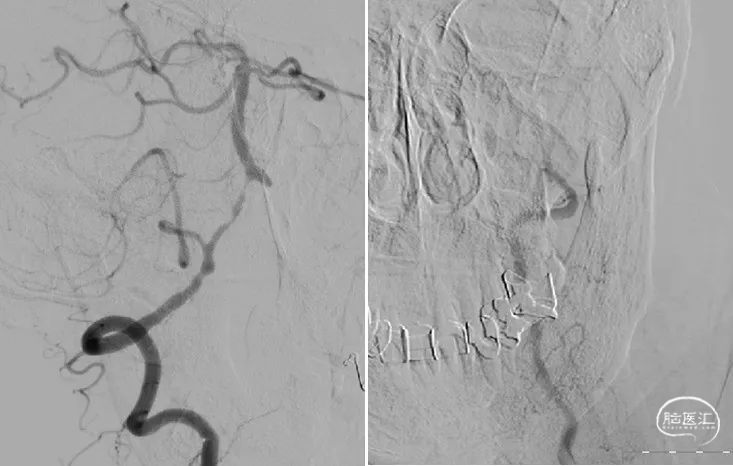

在颅内支撑导管支撑下,将0.014'' 300cm微导丝,通过狭窄节段将其放置在基底动脉中段。将2.0mm*10mm球囊打起预扩狭窄部位,然后更换赛诺神畅 颅内药物洗脱支架NOVA DES® 2.5*10mm延微导丝顺利通过狭窄节段,再次造影见定位准确,缓慢扩张球囊释放支架。

术后影像

术后即刻影像及患者术后情况:

造影见狭窄位置狭窄解除,支架贴壁良好,后循环各分支动脉显影良好。术后次日患者行走不稳情况明显改善,术后1月随访患者行走如常,未再发头晕。